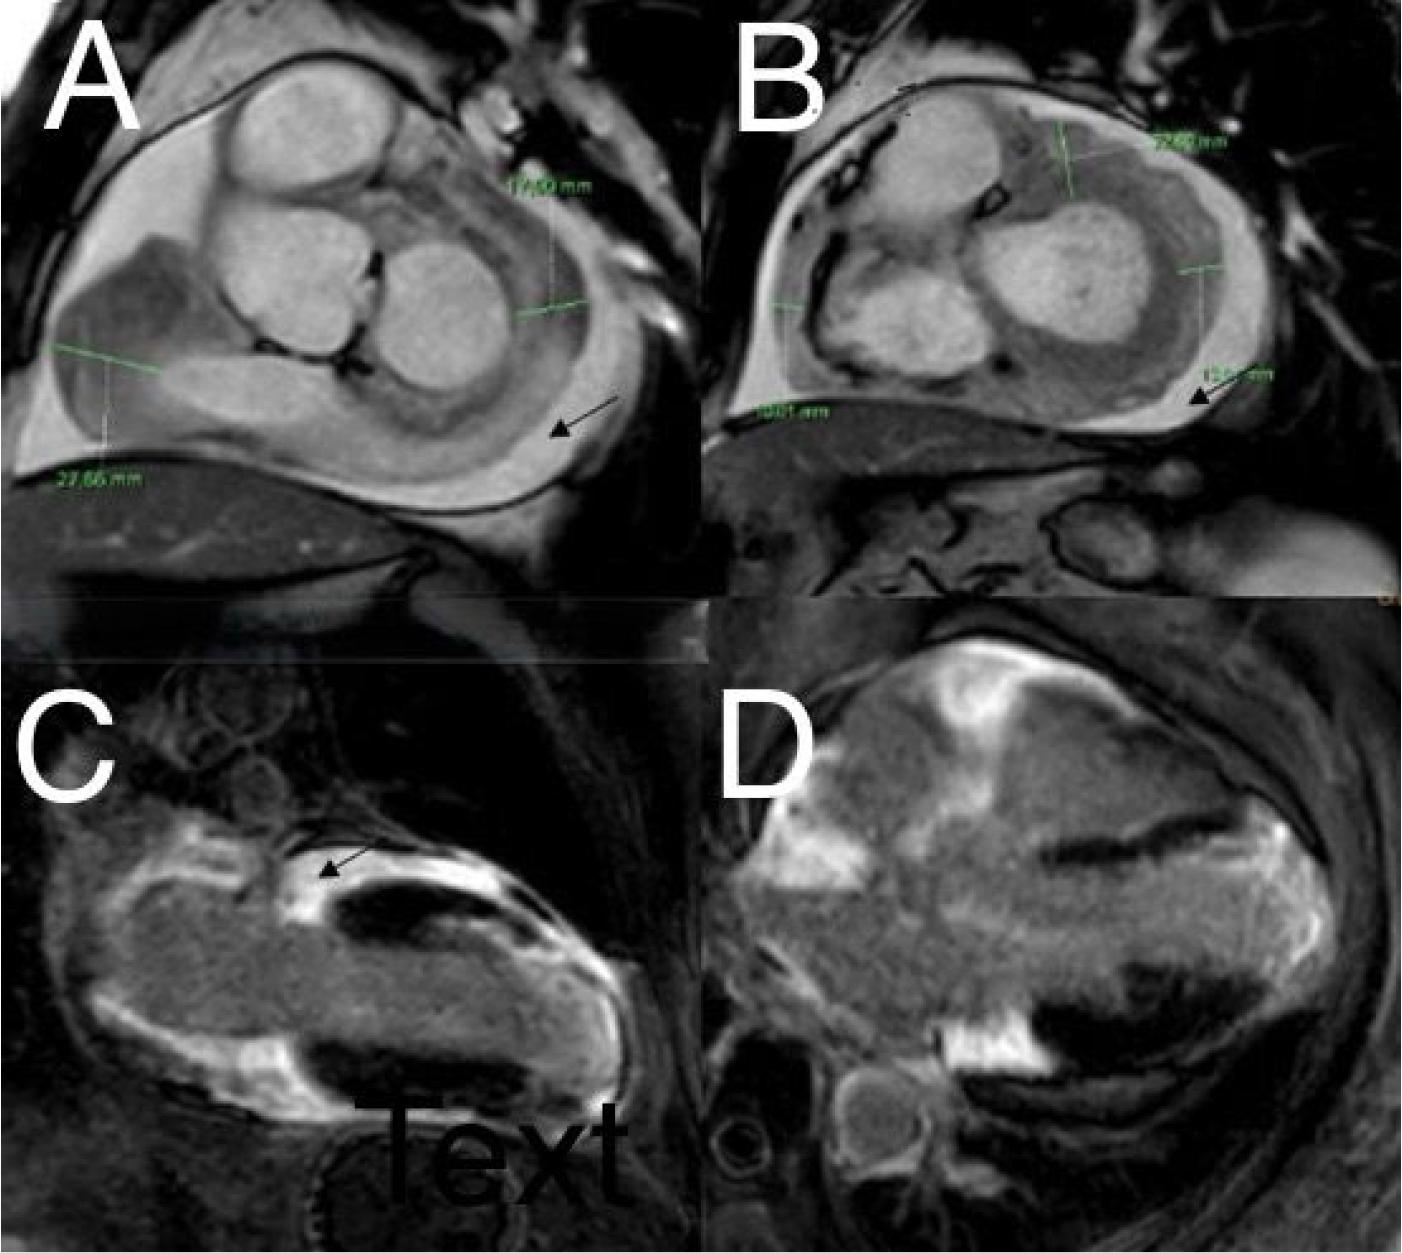

Figure 1